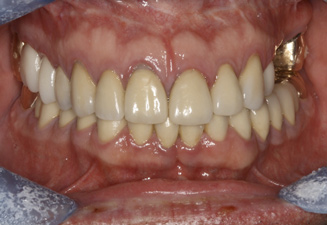

Fig 8. Failing dentition in an 82-year-old patient currently diagnosed with tardive dyskensia.

Figure 8

Fig 9. Transition line could not be hidden due to uncontrolled contortions of the facial musculature.

Figure 9

Fig 10. Recording a repeatable centric position was virtually impossible for this patient due to spasticity of the masticatory system. Among the compromises necessary in creating an occlusal scheme was to revert to a monoplane approach.

Figure 10

Fig 11. Recording a repeatable centric position was virtually impossible for this patient due to spasticity of the masticatory system. Among the compromises necessary in creating an occlusal scheme was to revert to a monoplane approach.

Figure 11

A patient with tardive dyskensia, for example, may experience dramatic changes in expressive facial activity and corresponding dysfunction in the muscle memory needed to repeat a centric position.19,20 Figure 8 and Figure 9 show an 82-year-old patient who had previously been treated for depression, had a failing dentition, and was diagnosed with tardive dyskensia. Extreme uncontrolled contortions of the facial musculature were evident in the patient when attempting to record a high smile line; removal of enough maxillary bone to hide the transition line was impossible. Dramatic compromises in occlusal scheme may be necessary to achieve even a moderately successful result; yet the implant approach realistically may be the only way to offer any functional improvement (Figure 10 and Figure 11).